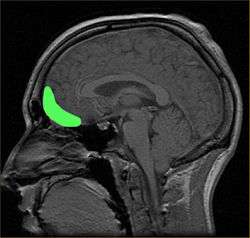

Approximate location of the OFC shown on a sagittal MRI | |